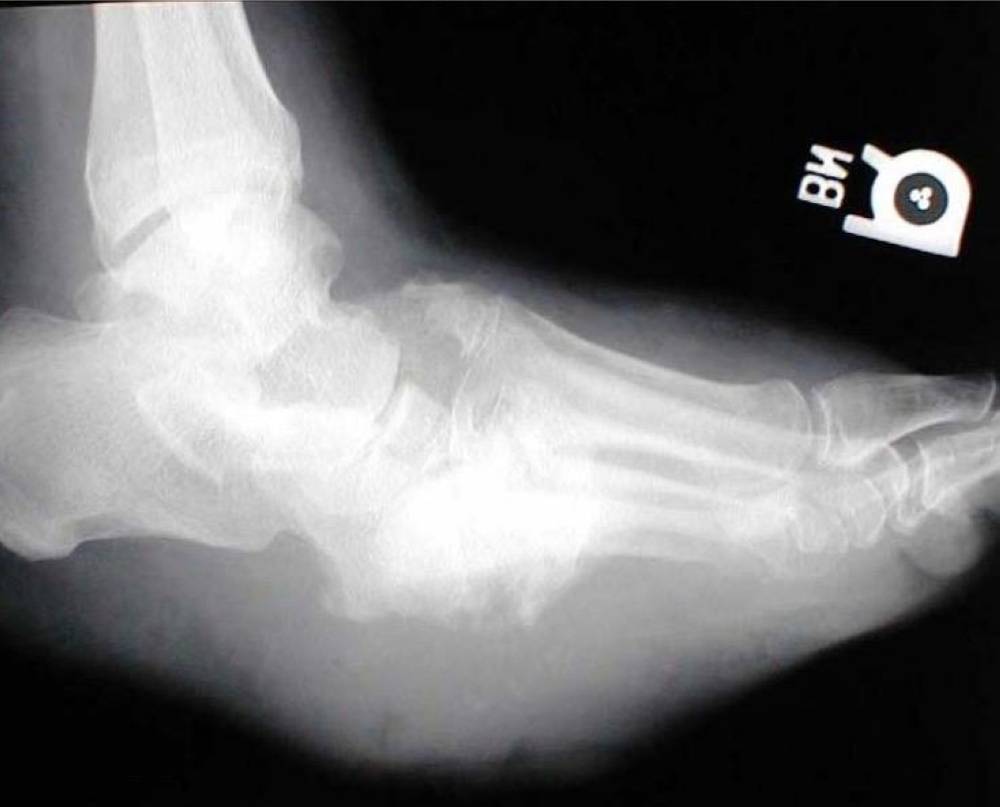

أوضح بادحدح بأن قدم شاركوت أو (كسور القدم السكرية) عبارة عن حالة تصيب الأشخاص المصابين باعتلال وتلف الأعصاب الطرفية السفلية وفقدان الإحساس، مما يضعف العظم ويجعله عرضة للكسور. وتختلف تماما عن الكسور الناتجة من الإصابات والحوادث، وسميت بقدم شاركوت نسبة للطبيب الفرنسي الذي اكتشفها.

أبان بادحدح بأن قدم شاركوت في المراحل الأولى قد تشبه بعض الأمراض كالجلطات الوريدية، التهاب خلوي، النقرس أو تسوس العظام، مما يصعب من تشخيصها في المراحل الأولى لغير المختص، وخاصة أن الأشعة السينية تكون سالبة ولا تدل على وجود كسور، موضحا أنه كلما كان تشخيص قدم شاركوت في المراحل الأولى، كلما قلت نسبة المضاعفات وتقل نسبة التدخل الجراحي، ولذلك على مريض السكر إذا لاحظ هذه الأعراض أن يتوجه لطبيب القدم والكاحل لمعاينة الحالة وتشخيصها.